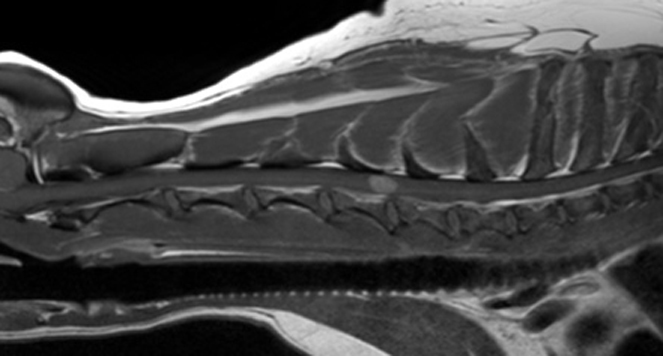

Angela Fadda received funding from Langford Trust for a study entitled ‘Nerve growth factor in cervical and thoracolumbar canine intervertebral disc herniation and its association with spinal pain: a preliminary study’

Tom Harcourt-Brown  Patient demographics and behavioural risk factors in canine episodic movement disorders

Episodic movement disorders in dogs are being described with increasing frequency. Some breed-specific forms have been associated with genetic mutations or have specific triggers (such as emotional arousal), but most are idiopathic and have not been associated with a trigger. Stress has been strongly implicated as a trigger in similar human conditions, and our clinical experience supports this in dogs; meaning behavioural therapy might be very useful in managing this lifelong condition.